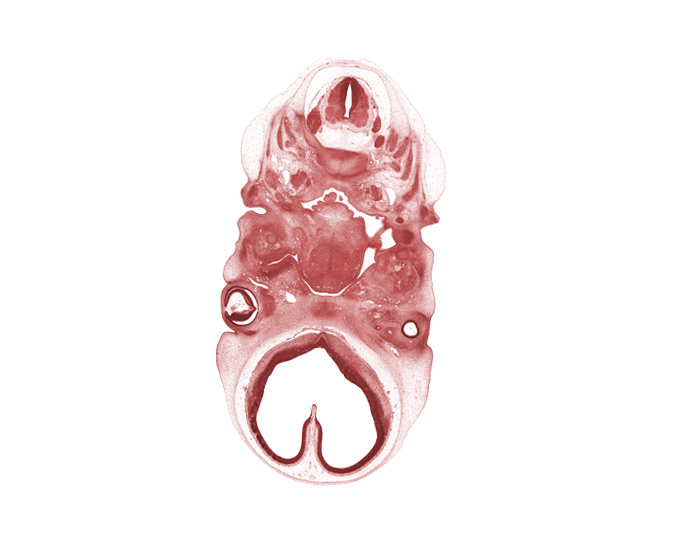

Carnegie Embryo #4430 | Location: 12-22

Keywords: C-1 / C-2 intervertebral region, C-2 dorsal root, C-2 spinal ganglion, C-2 spinal nerve, C-3 spinal ganglion, basisphenoid condensation, centrum of C-2 vertebra (axis), edge of intraretinal space (optic vesicle cavity), external acoustic meatus, glossopharyngeal nerve (CN IX), hypoglossal nerve (CN XII), inferior ganglion of vagus nerve (CN X), maxillary venous plexus, neural arch of C-2 vertebra (axis), optic stalk (CN II), palatine shelf, precardinal vein, root of tongue, spinal accessory nerve (CN XI), telencephalon medium, vertebral artery

Source: The Virtual Human Embryo.